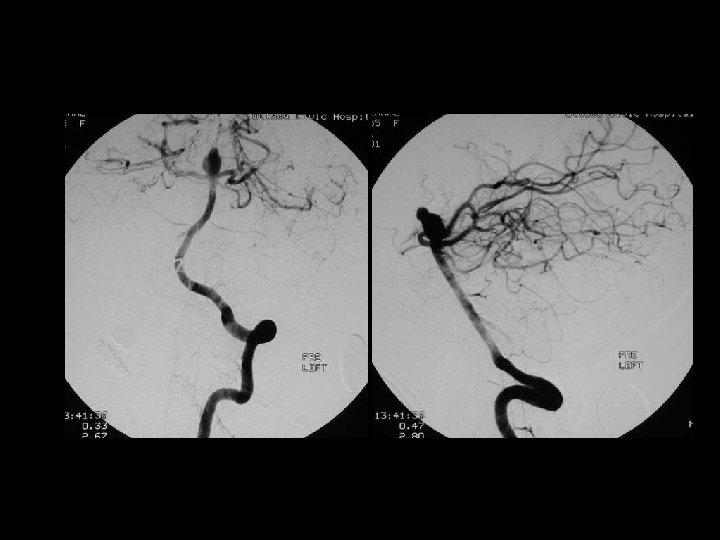

POST TRAUMATIC SEQUELAE n Carotid-cavernous fistula(CCF) n Dissection/pseudoaneurysm n Infarction n Atrophy/encephalomalacia n Infection n Leptomeningeal cyst